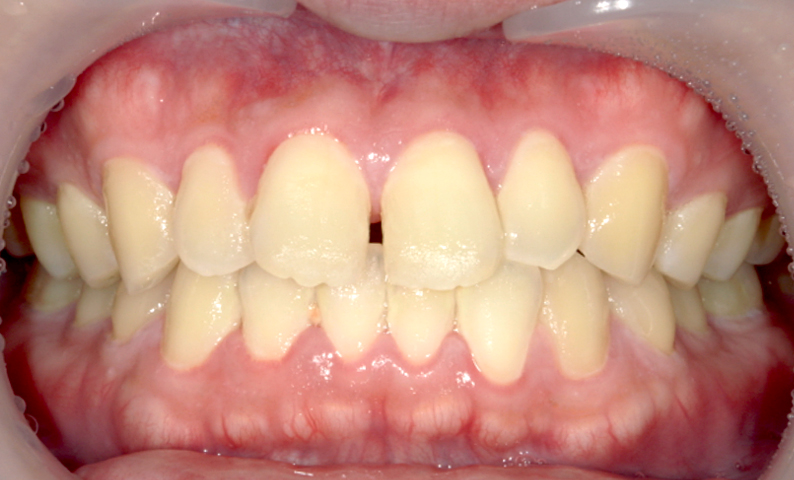

| 治療前 | 治療後 |

|---|---|

|